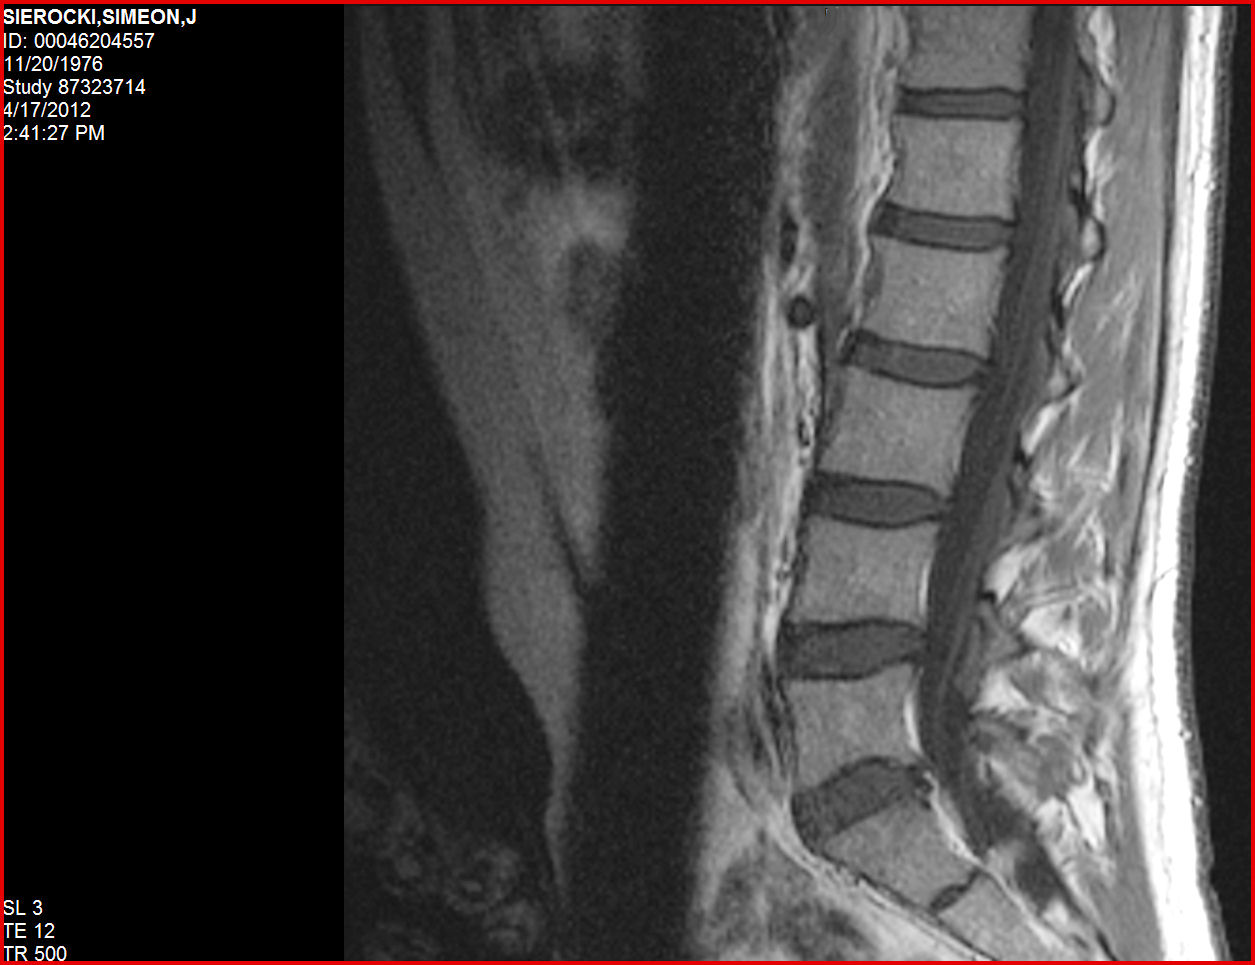

Lumbar Disc Herniation MRI Reading-Chiropractic Treatment ...

Lumbar Disc Herniation MRI Reading-Chiropractic Treatment - Whiplash Injury with Drunk Driver. Lumbar Spine Pain with Disc Protrusion MRI study - Motorcycle Accident - Duration: 4:20. Burt Chiropractic Rehabilitation Center 314 views. ... View Video